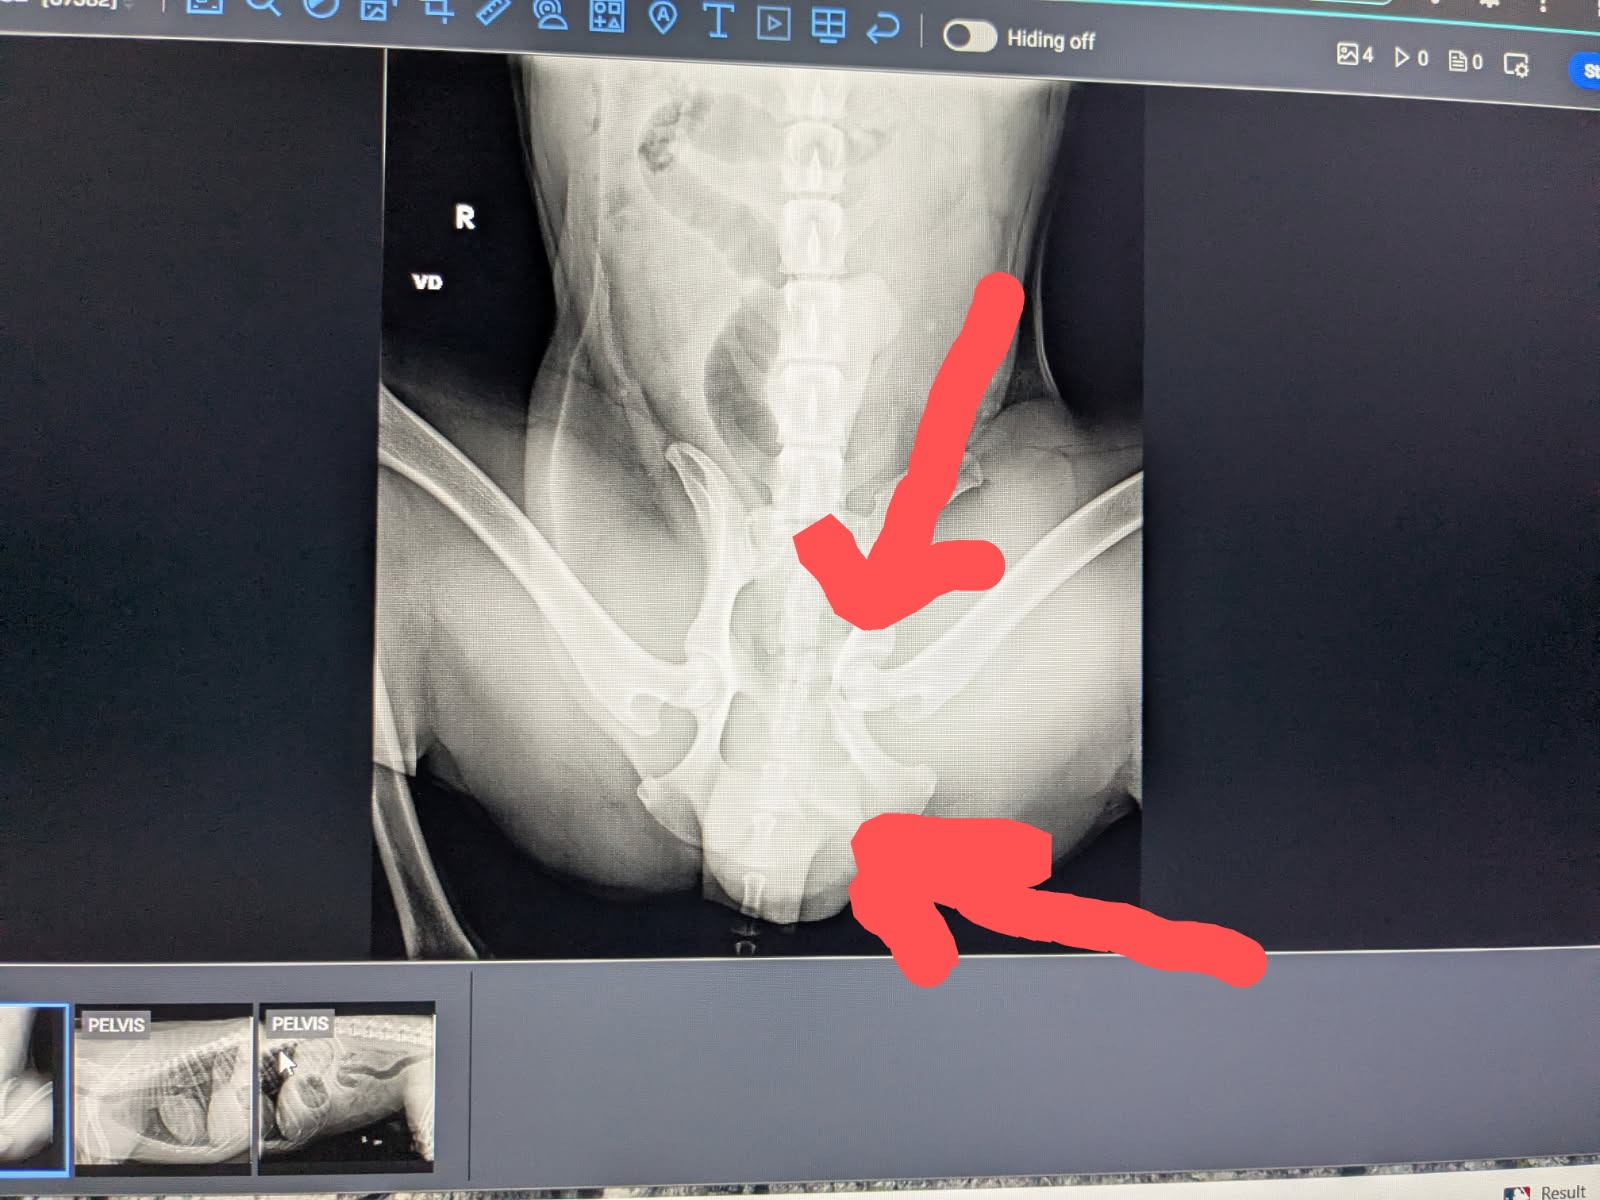

Dexter suffered a broken pelvis, road rash, and needed emergency surgery and a blood transfusion due to internal bleeding discovered during prep for orthopedic surgery in Wilmington. He is currently being stabilized with hopes for surgery on Monday or Tuesday, depending on his condition.